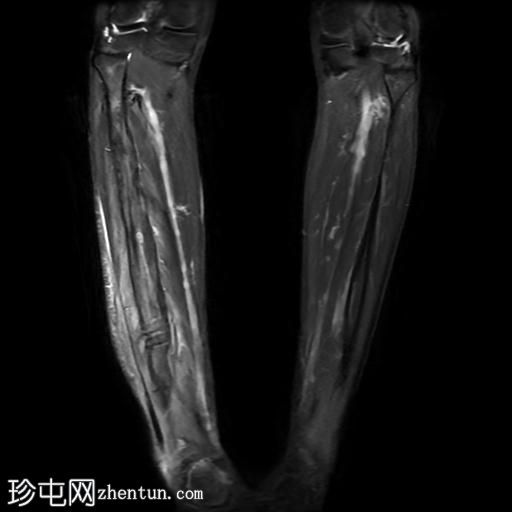

冠状位

T1加权像

腓骨可见广泛的骨髓水肿,伴有明显的皮质和骨膜增厚,整个腓骨均呈高信号。腓骨外侧中下三分之一交界处可见局灶性皮质破坏,并可见一条高信号瘘管延伸至周围皮肤。

此外,软组织(包括肌肉和皮下组织)也受累。

腓骨弥漫性骨髓信号异常,伴有明显的皮质和骨膜增厚,窦道自腓骨延伸至皮下区域。MRI 影像学表现符合腓骨骨髓炎。